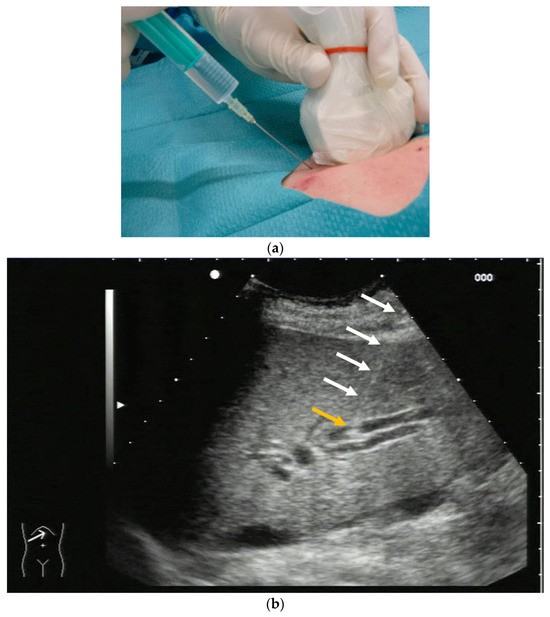

PTBD is commonly performed in the so-called “in plane technique” (Figure 1a,b).

(a) Puncture in plane. The needle is inserted at the centre of the small side of the transducer; (b) Needle tip (yellow arrow), body (white arrows), and target (bile duct) are depicted in one plane. The needle tip is kept in plane by very small movements of the transducer.

The needle is inserted at the narrow side of the transducer and advanced in the US plane. It can thereby be depicted on its whole trajectory. For a successful puncture, the interventionalist has to keep the needle shaft, tip, and target (bile duct) on the image at all times. Losing the tip or the target being out of sight will obviously prohibit a successful puncture. Not having the needle shaft in sight but seeing the tip and target means the further trajectory of the needle will miss the bile duct. Careful tiny corrections, either of the probe orientation or needle direction, must then be undertaken to have all three in sight during the procedure.